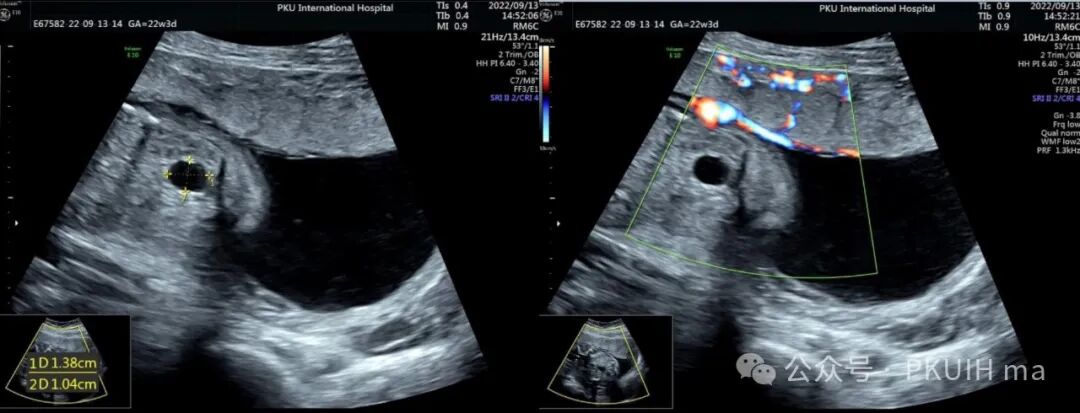

上图是一个孕22周筛查时发现的腹腔囊肿,在随访中发现有所增大。并在生后超声检查提示肠重复囊肿。通过产前超声图像囊壁增厚及囊壁回声增强特征支持肠重复囊肿